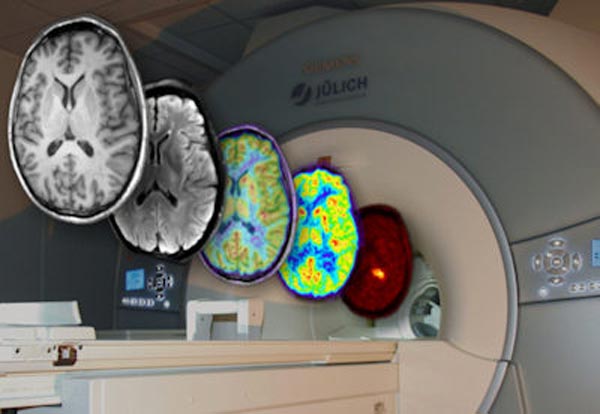

Tiefer Blick in die Gehirnfunktion

Wie das Gehirn die beeindruckende Vielfalt unseres Denkens, Fühlens und Handelns hervorbringt, wird seit Jahren mit bildgebenden Verfahren wie der…